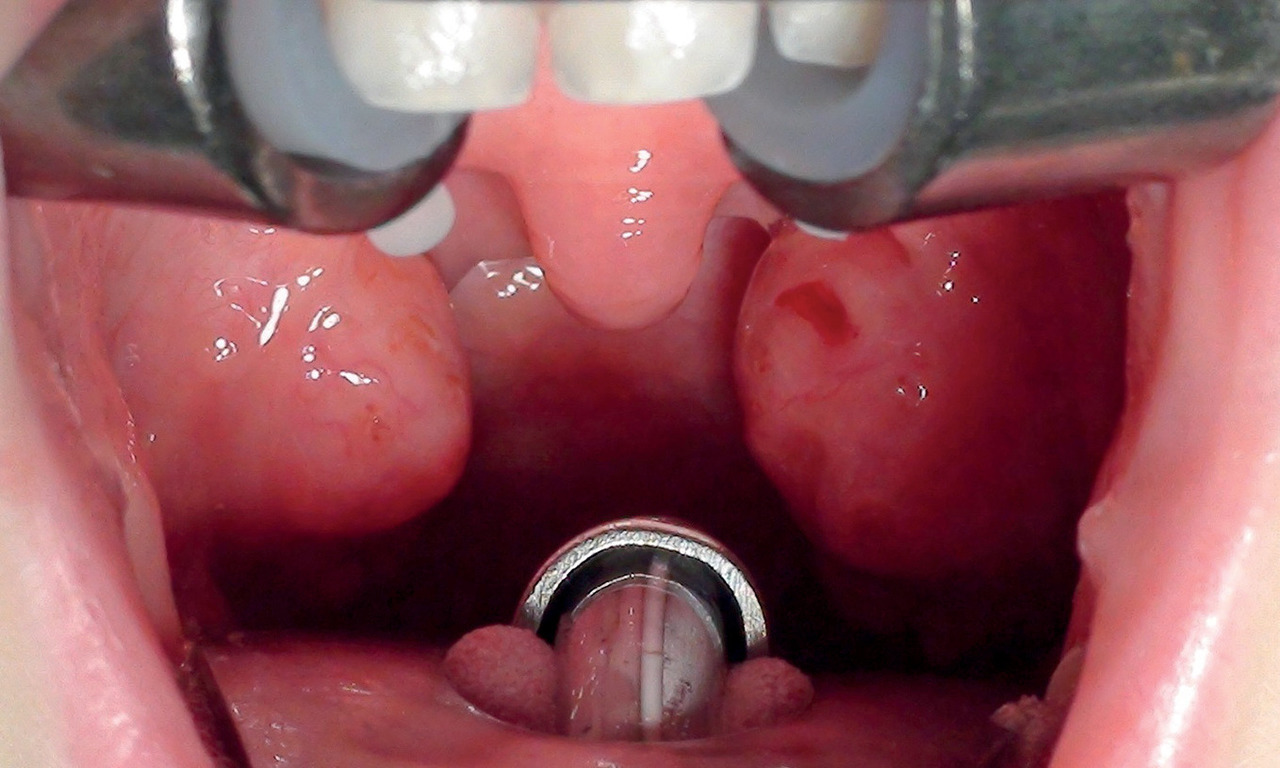

C’est une hypertrophie des amygdales et/ou des végétations dans la très grande majorité des cas (fig. 1). La première est en général cotée de 0 à 4 ;

– 0 : amygdales entièrement dans la loge ;

– 1 : petites, elles laissent apercevoir le pilier postérieur du voile, prenant moins de 25 % de l’espace ;

– 2 : elles en occupent entre 25 et 50 % ;

– 3 : entre 50 et 75 % ;

– 4 : amygdales jointives ou quasi jointives.3 L’hypertrophie des végétations adénoïdes, seule ou associée, est objectivée quand c’est nécessaire via une fibroscopie du cavum par voie nasale, réalisable à tout âge quand on dispose du matériel adapté.